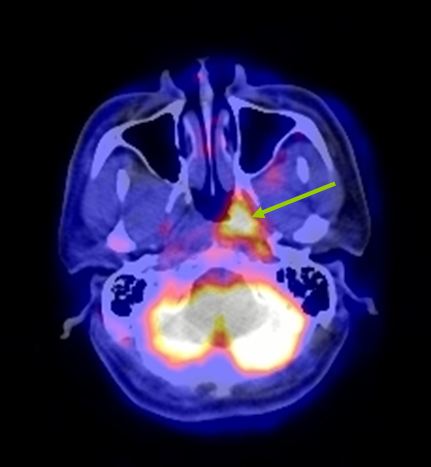

Mô phỏng tốt nhất trên PET/CT với hệ thống laser định vị 3 chiều. Vì PET/CT ghi hình dựa trên sự tập trung cao thuốc phóng xạ FDG vào các tế bào ung thư, cho hình ảnh chuyển hóa của khối u, sớm, chính xác hơn hình ảnh giải phẫu của CT đơn thuần (hình 1), xác định được mức độ xâm lấn của u cũng như phát hiện những di căn hạch kể cả với kích thước nhỏ ở mức độ phân tử, mức độ tế bào từ đó cho phép xác định thể tích xạ trị cũng như việc lập kế hoạch xạ trị được triệt để nhất (hình 2). Khi chụp mô phỏng: bệnh nhân trong tư thế nằm ngửa, cổ ưỡn sao cho đường thẳng giữa cằm - xương chũm vuông góc với mặt bàn; đầu bệnh nhân được giữ cố định bằng mặt nạ, tổng hợp từ loại chất dẻo đặc biệt.

Hình ảnh CT mô phỏng khó xác định được vị trí khối u

Hình ảnh PET/CT mô phỏng thấy rõ khối u vòm

Hình 1: Hình CT và PET/CT mô phỏng ung thư vòm.